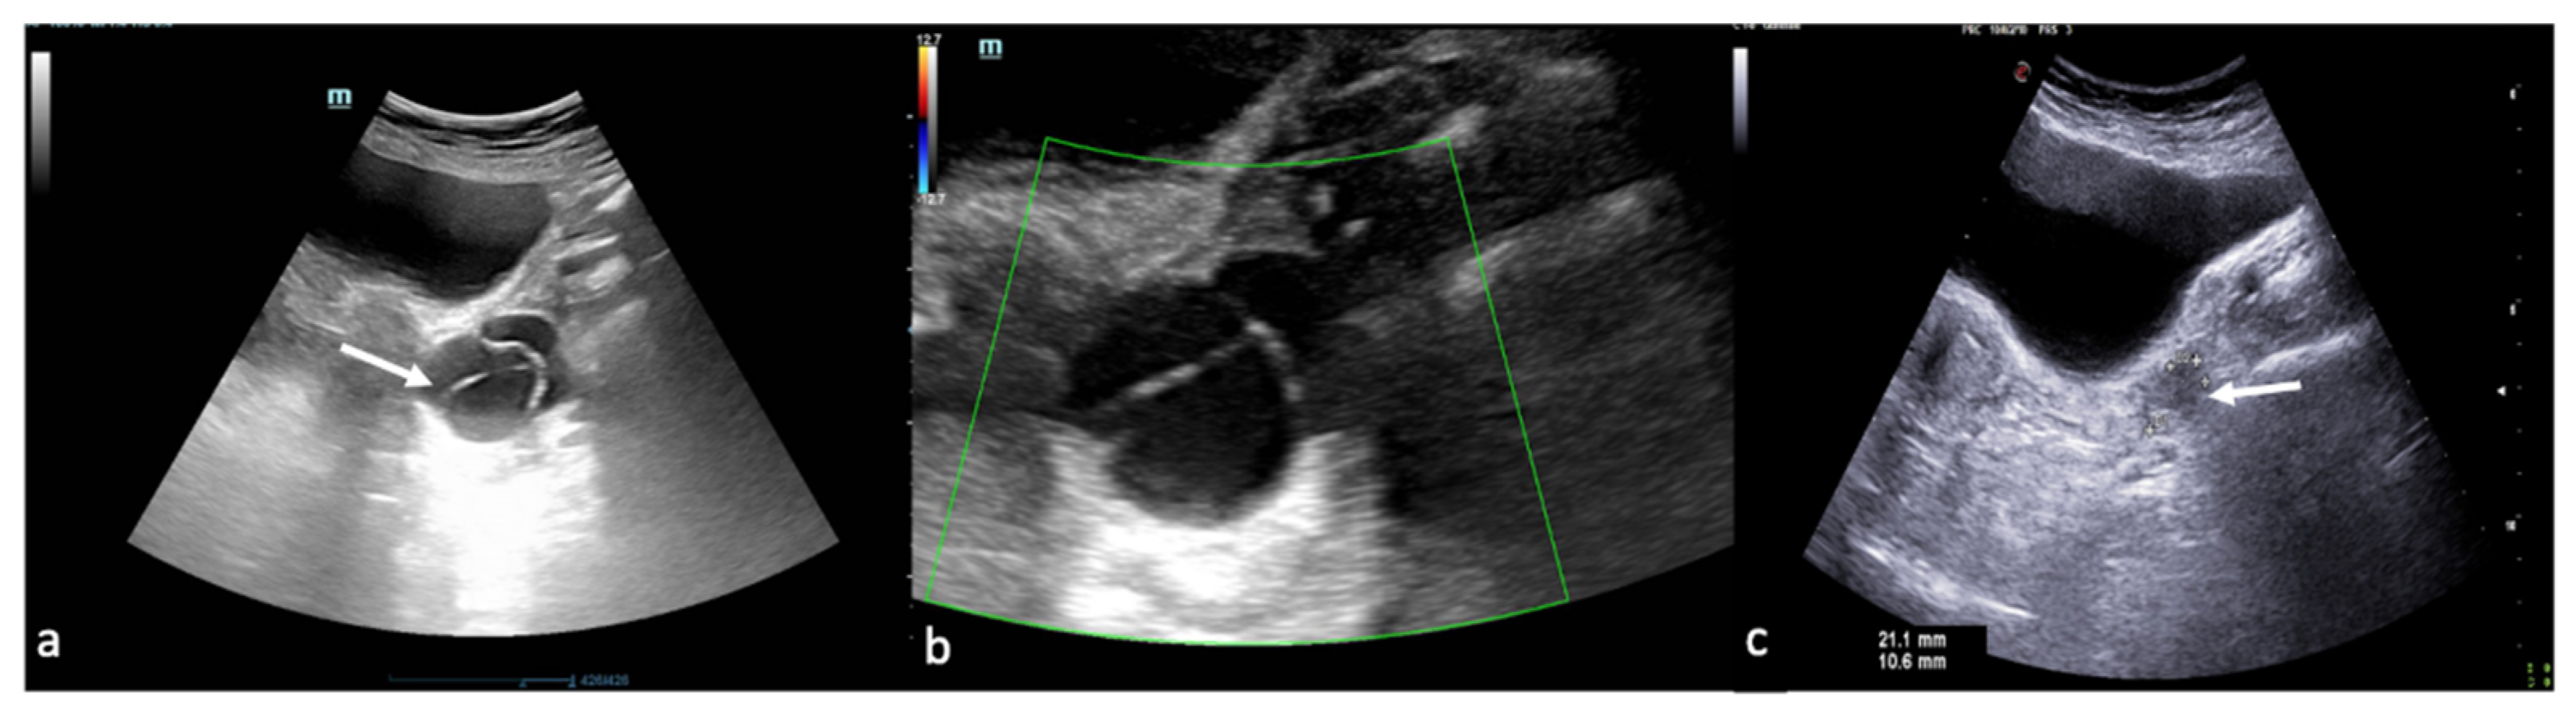

Figure 16. Thrombosis of the right gonadal vein. TSA–US scan of the left ovarian vein in axial (A) and longitudinal (B) view before delivery show the ovarian vein as a tubular structure with heterogeneous hypoechoic echotexture ((B) arrows), located superiorly to the ovary and anteriorly to the psoas muscle. Contrast-enhanced CT coronal image (C) was performed after delivery and confirmed the left gonadic vein thrombosis (red circle). Reprinted with permission from [46].